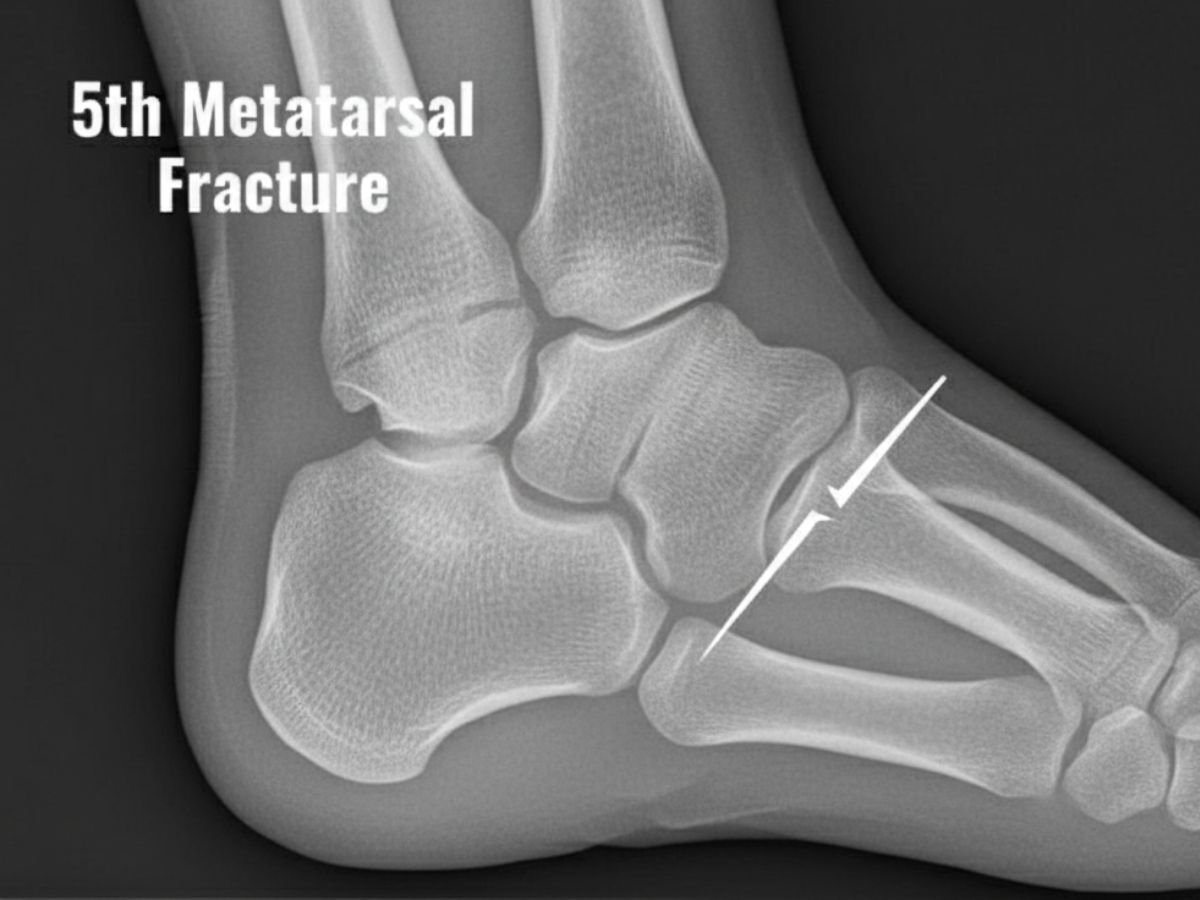

How is a hairline fracture of the fifth metatarsal identified?

A healthcare professional, including Dr. Kris A. DiNucci, DPM, FACFAS, will perform a bodily examination and might order imaging exams like X-rays or MRI to confirm the analysis.